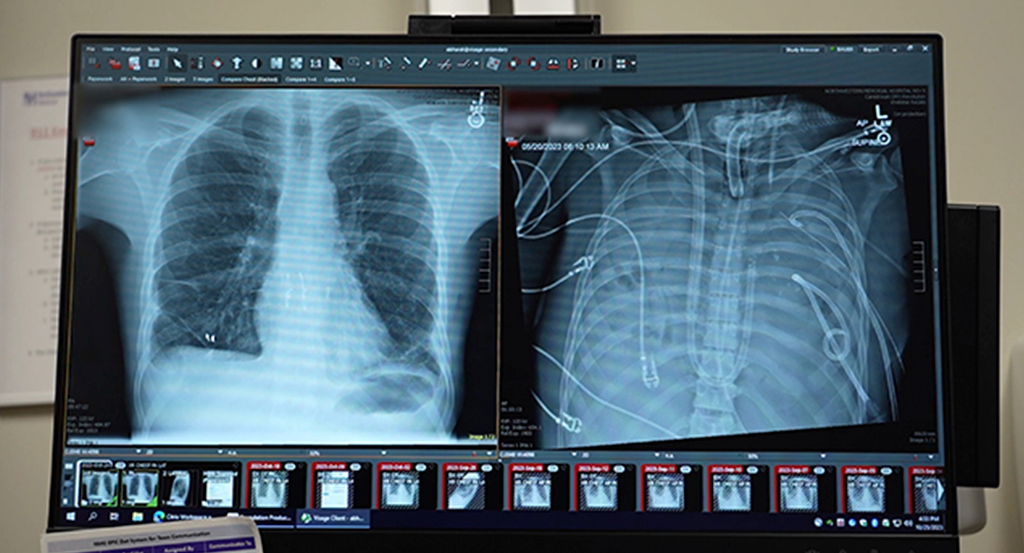

A cirurgia ocorreu em 2023, mas o caso só foi detalhado recentemente em uma publicação no periódico científico Med. O homem de 33 anos inicialmente apresentava complicações pulmonares causadas pela influenza. O quadro evoluiu rapidamente para um caso grave de pneumonia e síndrome do desconforto respiratório agudo.

As bactérias causadoras da infecção eram imunes aos antibióticos, e o estado do paciente piorava progressivamente. A função pulmonar entrou em colapso, o tecido do pulmão começou a se liquefazer, o homem sofreu uma parada cardíaca e desenvolveu insuficiência renal. Caso permanecesse com seus próprios pulmões, ele morreria.

Com essa inovação, os médicos mantiveram homem vivo por dois dias após a remoção dos pulmões. Durante esse período, sua condição apresentou melhoras significativas e o organismo começou a se recuperar da infecção, reduzindo os riscos do transplante.

Agora, três anos depois, o novo par de pulmões transplantados continua funcionando bem. O artigo que detalha o caso foi publicado em 30 de janeiro.